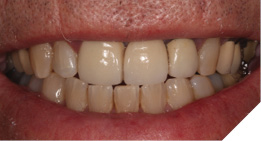

A 75-year-old male patient developed a problem with a tooth supported bridge for the upper right central and left central and lateral incisor teeth that had been in situ for more than twenty years. One of the supporting teeth had become loose and the referring dentist noticed the upper left abutment tooth was grossly carious and the three-unit bridge entirely supported by the upper right central incisor tooth.

Radiographic examination shows the upper left lateral incisor tooth has decayed through and through and the upper right central incisor tooth is heavily root treated and filled (Figs. 1-2).